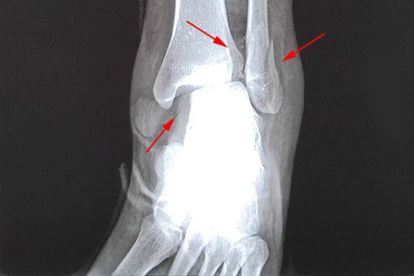

骨裂后需立即通过石膏、支具或外固定架限制患肢活动,避免骨折端移位。上肢骨裂常用前臂石膏,下肢骨裂需配合拐杖减少负重。固定时间通常为4-8周,期间需定期复查X线观察愈合情况。若固定不当可能导致畸形愈合或延迟愈合。